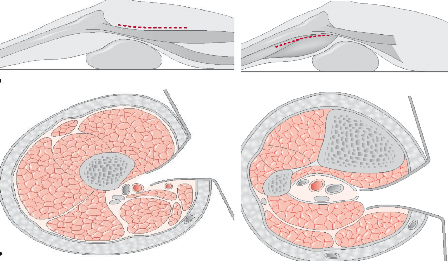

+ Tổn thương động mạch khoeo kèm theo gãy xương quanh gối, sai khớp gối: đặt bệnh nhân nằm ngửa, khớp gối gấp 30o. Tùy vị trí tổn thương động mạch khoeo trên gối hoặc dưới gối để mở rộng vết mổ (hình 2.1 A,B).

A B

Hình 2.1: Đường mổ động mạch khoeo trên (A) và dưới (B) khớp gối Đường mở rộng là kết hợp giữa hai đường mổ trên cho phép bộc lộ

kiểm tra toàn bộ động mạch khoeo.